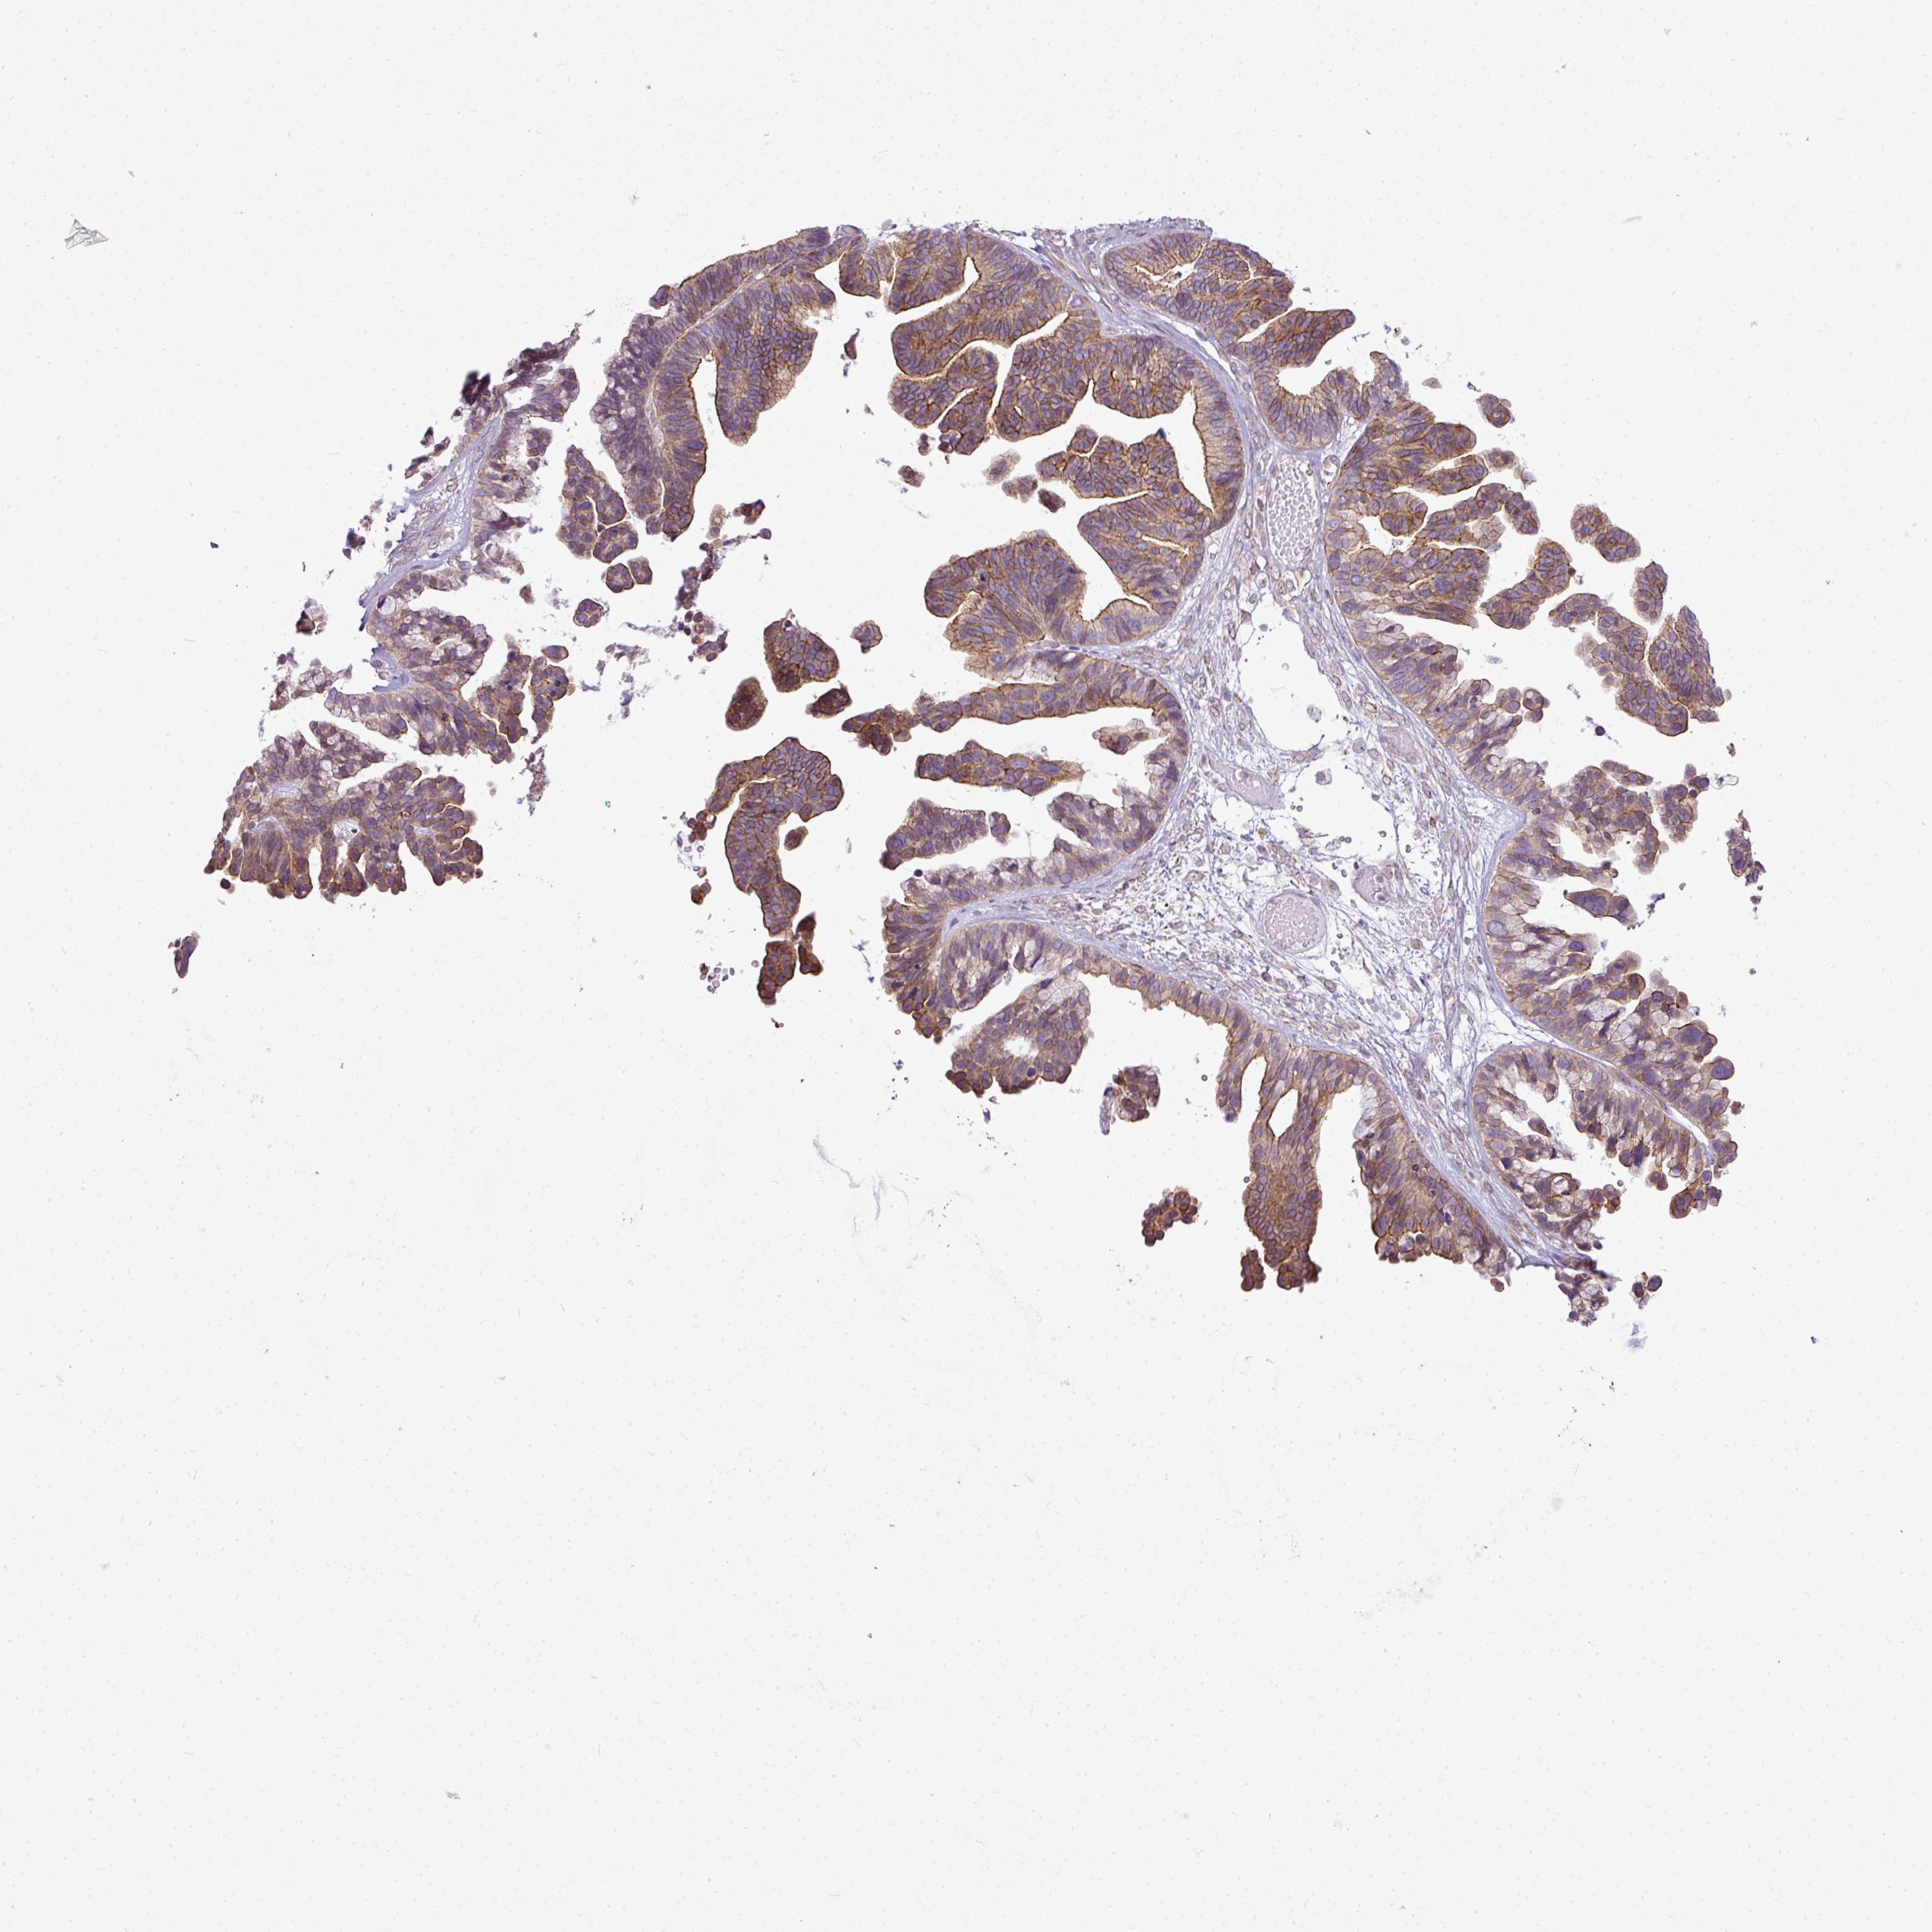

OVARIAN CANCER - Protein expressioni

A mouse-over function shows sample information and annotation data. Click on an image to view it in a full screen mode. Samples can be filtered based on level of antibody staining by selecting one or several of the following categories: high, medium, low and not detected. The assay and annotation is described here.

Note that samples used for immunohistochemistry by the Human Protein Atlas do not correspond to samples in the TCGA dataset.

Antibody stainingi

Antibody staining in the annotated cell types in the current human tissue is reported as not detected, low, medium, or high, based on conventional immunohistochemistry profiling in selected tissues. This score is based on the combination of the staining intensity and fraction of stained cells.

Each image is clickable and will lead to virtual microscopy that enables deeper exploration of all samples and also displays staining intensity scores, fraction scores and subcellular localization as well as patient and tissue information for each sample.

Antibody HPA046772

Antibody HPA049489

Cystadenocarcinoma, serous, NOS

Carcinoma, NOS

Cystadenocarcinoma, mucinous, NOS

Carcinoma, endometroid